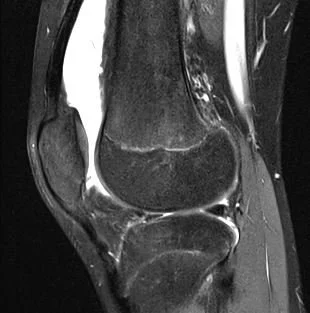

Rare and pediatric disease trials come with complex challenges that require specific expertise and experience. We have the radiology exerts to support the specific requirements of pediatric clinical trials. Many rare diseases affect children, and pediatric trials bring additional challenges.

They require specific protocols, involve additional regulations and demand expertise and experience. BICL’s experts are experienced in oncology, MSK and other pediatric disorders including growth plate disturbance, bone age and osteochondroma.